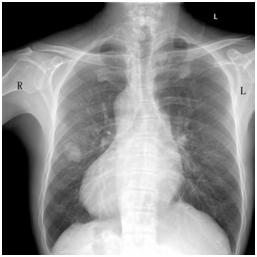

患者胸部正位X线片

“镜面人”是完全性内脏反位(situs inversus totalis,SIT)的俗称,是一种罕见的先天性畸形,临床上通常表现为胸腔、腹腔器官及解剖结构的完全左右反位。SIT通常不影响人的健康,但是一旦患病就会给治疗特别是手术治疗带来巨大障碍。因为解剖结构的变异会颠覆医生原有的医学常识,影响手术操作的顺利进行,从而严重影响预后。SIT的发生率约为1/20000到1/8000,合并肺癌的SIT则更为罕见。据PubMed文献报道,SIT合并肺癌全球范围仅25例,左肺16例(64%),右肺9例(36%)。25例病人中只有16例接受了手术治疗,12例(75%)左肺,4例(25%)右肺。在这16例手术中,75%采用了传统的开胸手术,只有25%为胸腔镜治疗。